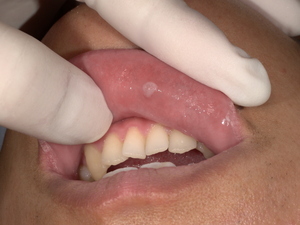

画像: 施術前の下唇のしこり(before)

こちらの画像は、患者様が最初に来院された際に撮影した下唇のしこりの状態です。しこりは約6㎜程で、唇の内側に小さな膨らみが確認できます。痛みはなく、色も健康な組織とほぼ同じですが、しこりが気になるということで治療を希望されました。

「下唇ににしこりがあるがいたみはない。がんかもしれない」とご相談いただきました。

拝見すると、下唇に6㎜程の小さなしこりが1つありました。

しこりはわずかに硬くなっていましたが、痛みなどの自覚症状はありませんでした。周囲の健康な組織との境界ははっきりしていて、表面は滑らかな質感で、しこり部分以外は色味も健常な状態でした。

下唇に6か月前からしこりがあり、治ったり、しこりが出来たり繰り返しているという。きっかけは、とある日、唇を噛んでしまったことから、しこりができ始めたという。痛みはないとのことです。